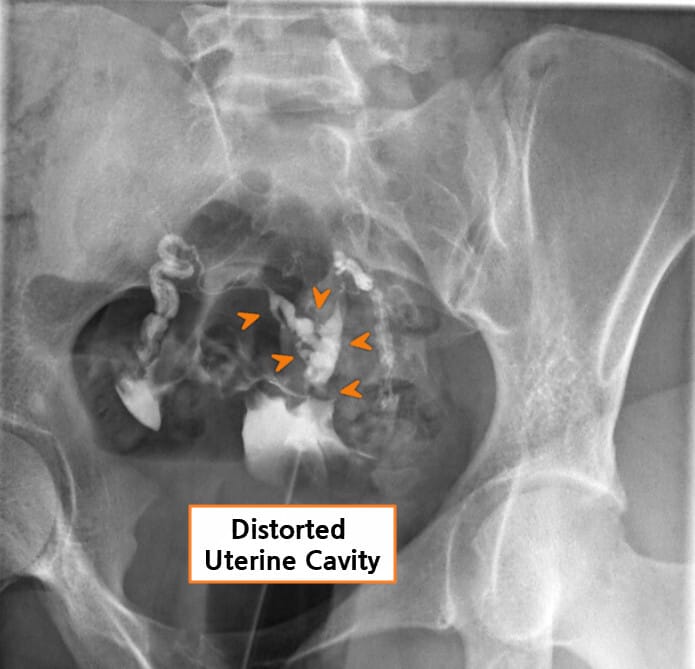

| 자궁난관조영술(HSG) |

| – 자궁강의 불규칙한 윤곽, 충만 결손(filling defect), 자궁강 일부 또는 전부의 소실이 관찰됩니다. |